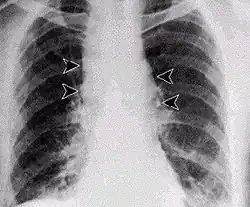

- Forma pulmonară (boala scărmănătorilor de lână) calea de pătrundere a sporilor bacilului în organism fiind plămânul, boala se manifestă prin tuse, febră mare, frisoane, insuficiență respiratorie, lichidul de secreție răspândit prin tuse fiind foarte infecțios. Este o formă gravă a bolii cu o mortalitate ridicată prin septicemie, între 3 și 6 zile după infectare.